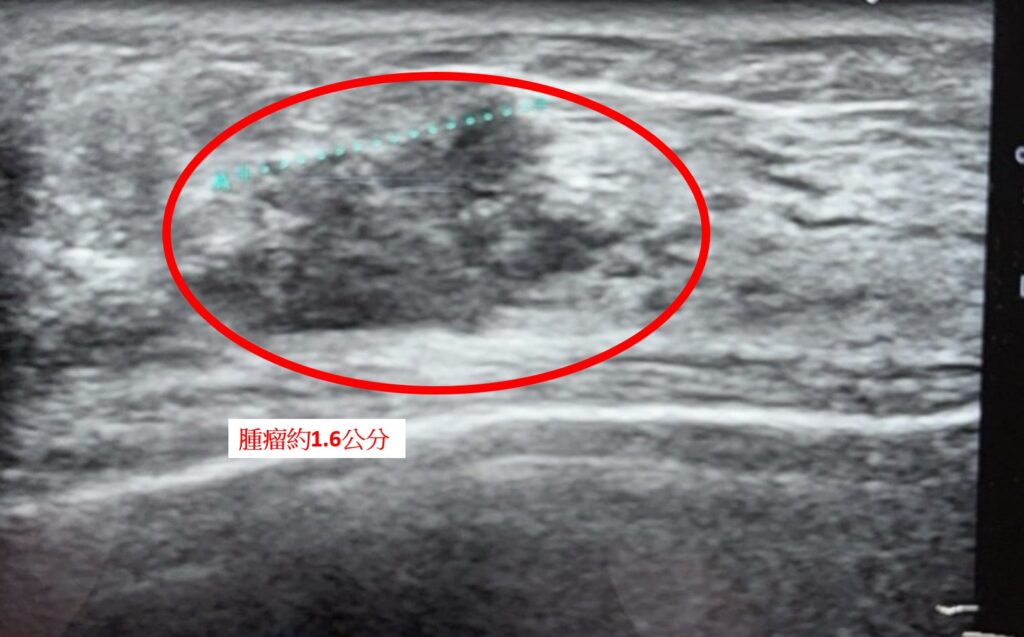

中醫大新竹附醫乳房外科主任古君平表示,所謂「多發性乳癌」,是指在同一側乳房中出現兩處以上、甚至分布於不同象限的腫瘤病灶。此案例影像檢查中,右邊乳房至少可見三處病灶,最大約1.6公分,最小約0.6公分。由於多發性腫瘤可能在影像未顯現的區域仍存在潛在癌細胞,臨床上通常建議進行乳房全切除,以降低殘留與復發風險。